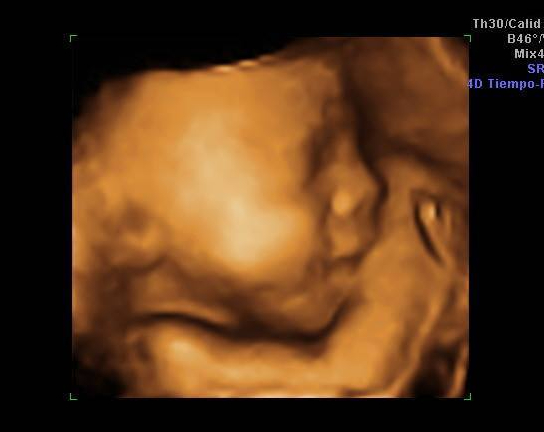

¿Es percepción o nacen más bebés en Sonora?

Pasa que hay etapas en las que me da la impresión que nacen más bebés. Es como si mi alrededor se llenara de mujeres embarazadas, de personas con pequeños en brazos y Facebook de fotografías donde revientan un globo del que salen papelitos rosas o azules que revelan el sexo de un bebé que vieneSigue leyendo «¿Es percepción o nacen más bebés en Sonora?»